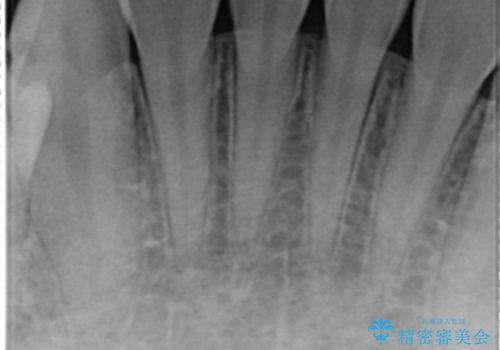

虫歯をしっかりと治療したのち、オールセラミッククラウンによる補綴治療を行いました。

クラウンの種類:オールセラミッククラウン スタンダード

シェード:NW0